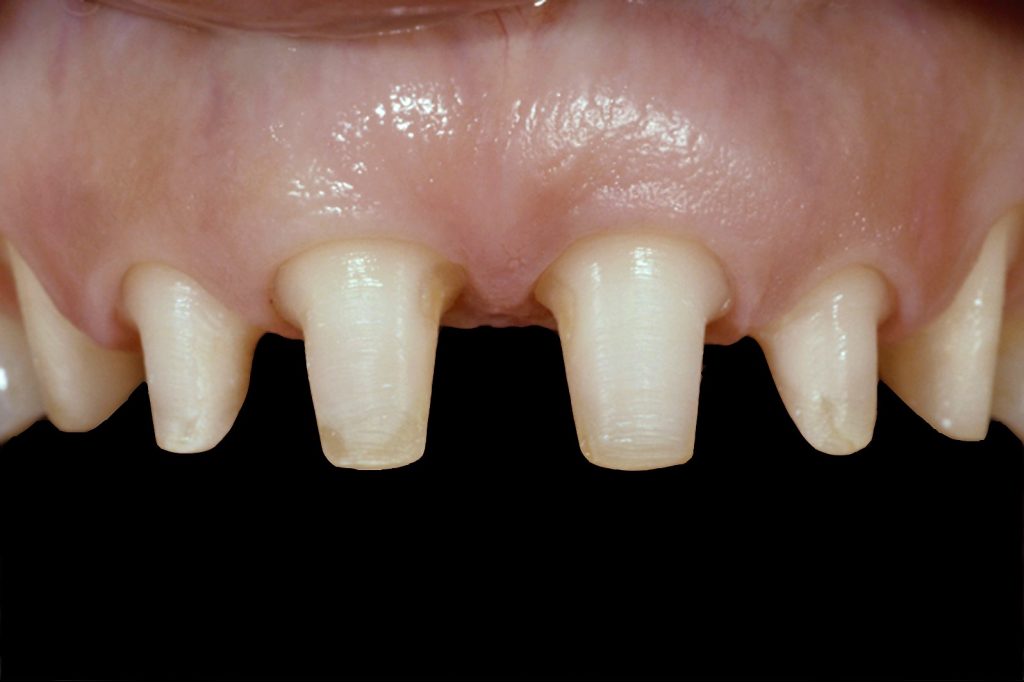

Structurally compromised teeth: Yes

Splinting teeth that are structurally compromised (i.e., lacking adequate tooth structure or short preps) is similar to double abutting multiple-unit FPD restorations for added structural stability. Although it must be said that if the tooth is that structurally compromised, it might be advantageous to consider removal of said tooth and replacement with an implant.